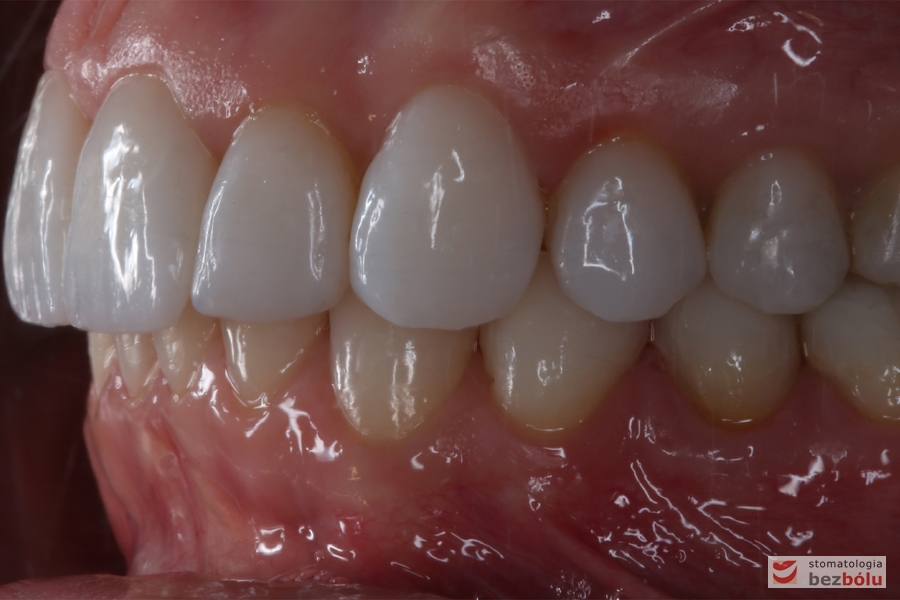

Lewa strona w zgryzie - zachowane pierwsze klasy kłowa i Angle'a

Lewa strona w zgryzie – zachowane pierwsze klasy kłowa i Angle’a